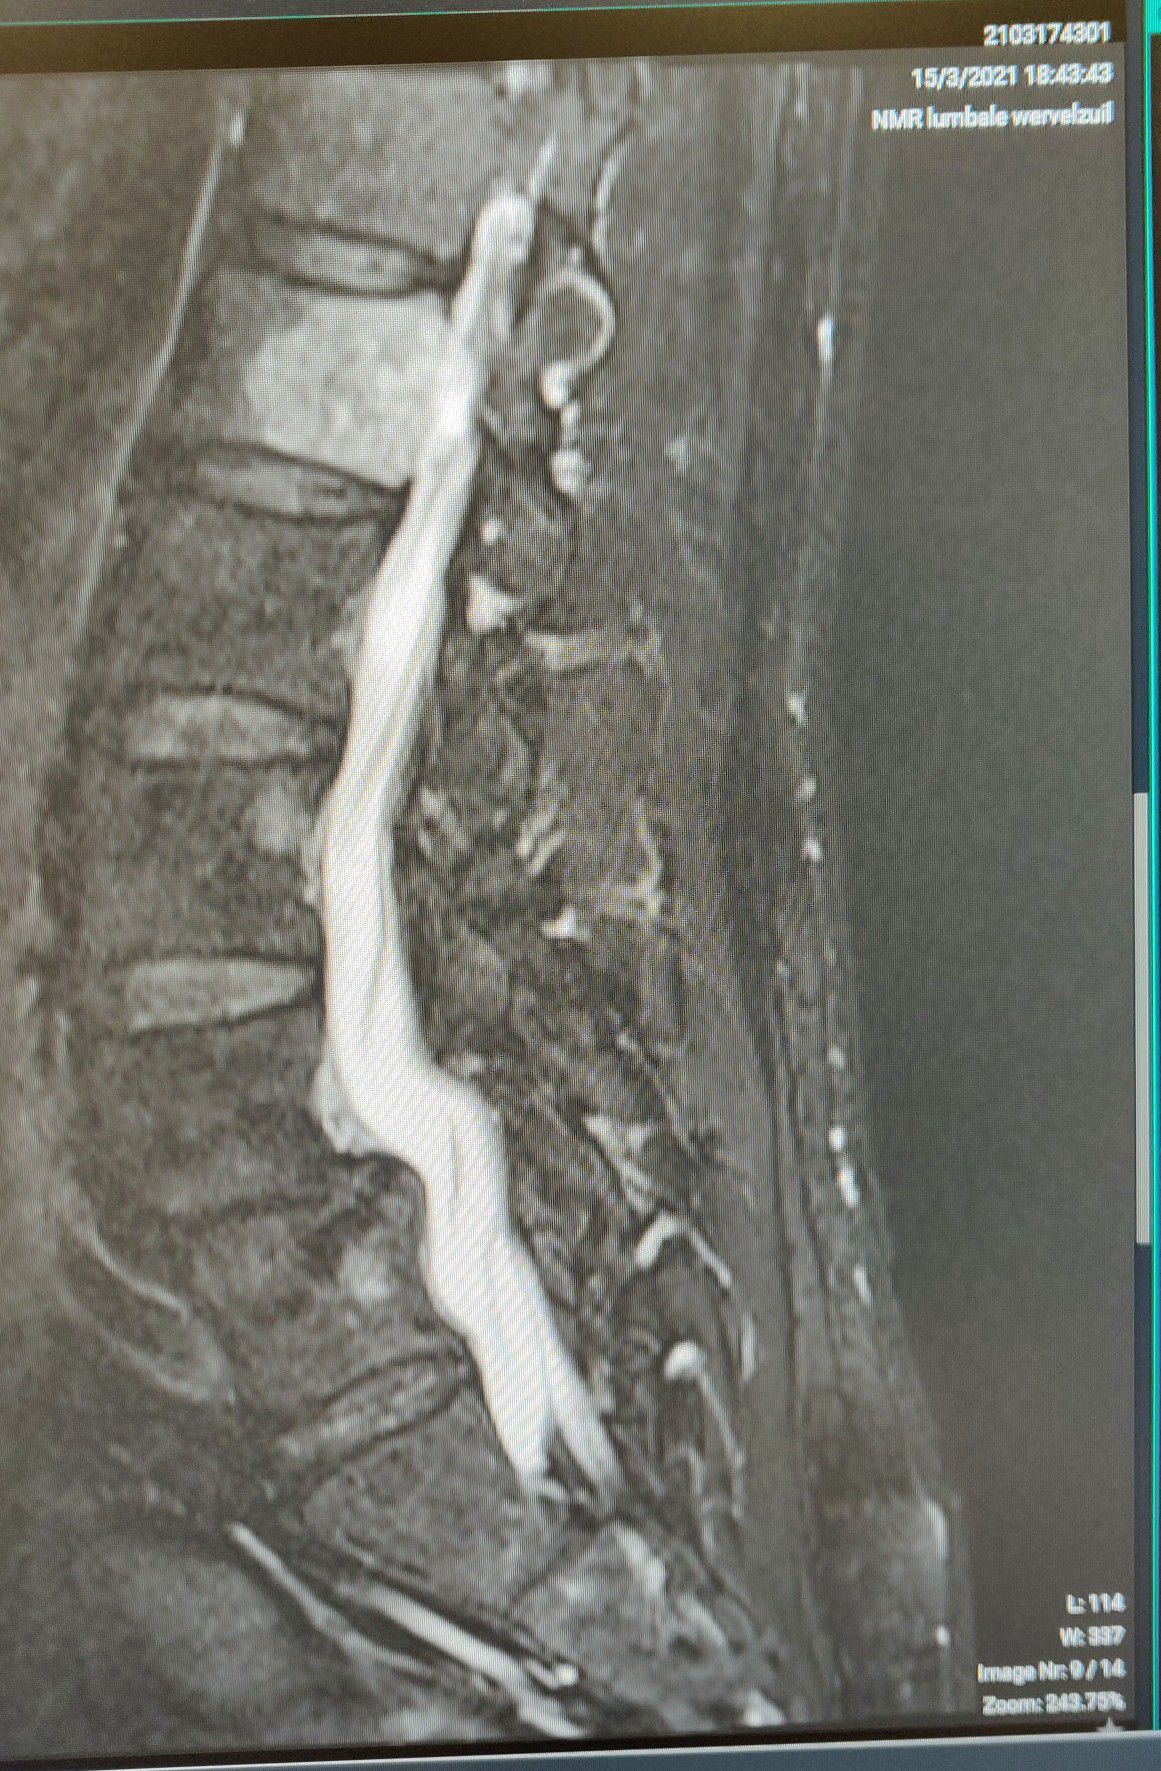

50y old male comes in my osteopathy clinic with upper lumbar backpain after reaching in his trunk. After 3 consults his backpain is gone, but has a numb feeling in his upper medial thigh. Not his groin. Patient is known with antherolysthesis L4-L5 for already 10 years. Did you see the real cause of his paresthesia?

Real cause is a growing haemangioma in the upper lumbar region, affecting his femoral branch of his n genitofemoralis